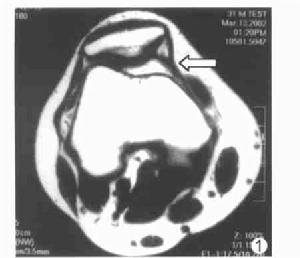

收肌結節內側髕股韌帶在顯示收肌結節和髕骨上部的橫軸像顯示最佳,顯示率為95%,表現為起自收肌結節,向前經過股內斜肌肌腱止點深面和下面止於髕骨內側緣的平滑的低信號條帶樣結構。以髕骨內緣止點處最厚,向收肌結節方向逐漸變薄(圖1)。冠狀像一般很難將該韌帶與周圍的其他結構區分開來。矢狀像有時可以顯示內側髕股韌帶,表現為內側髕脛韌帶深面的低信號帶樣結構,向內側逐漸變窄、變薄,止於股骨內側髁的收肌結節。